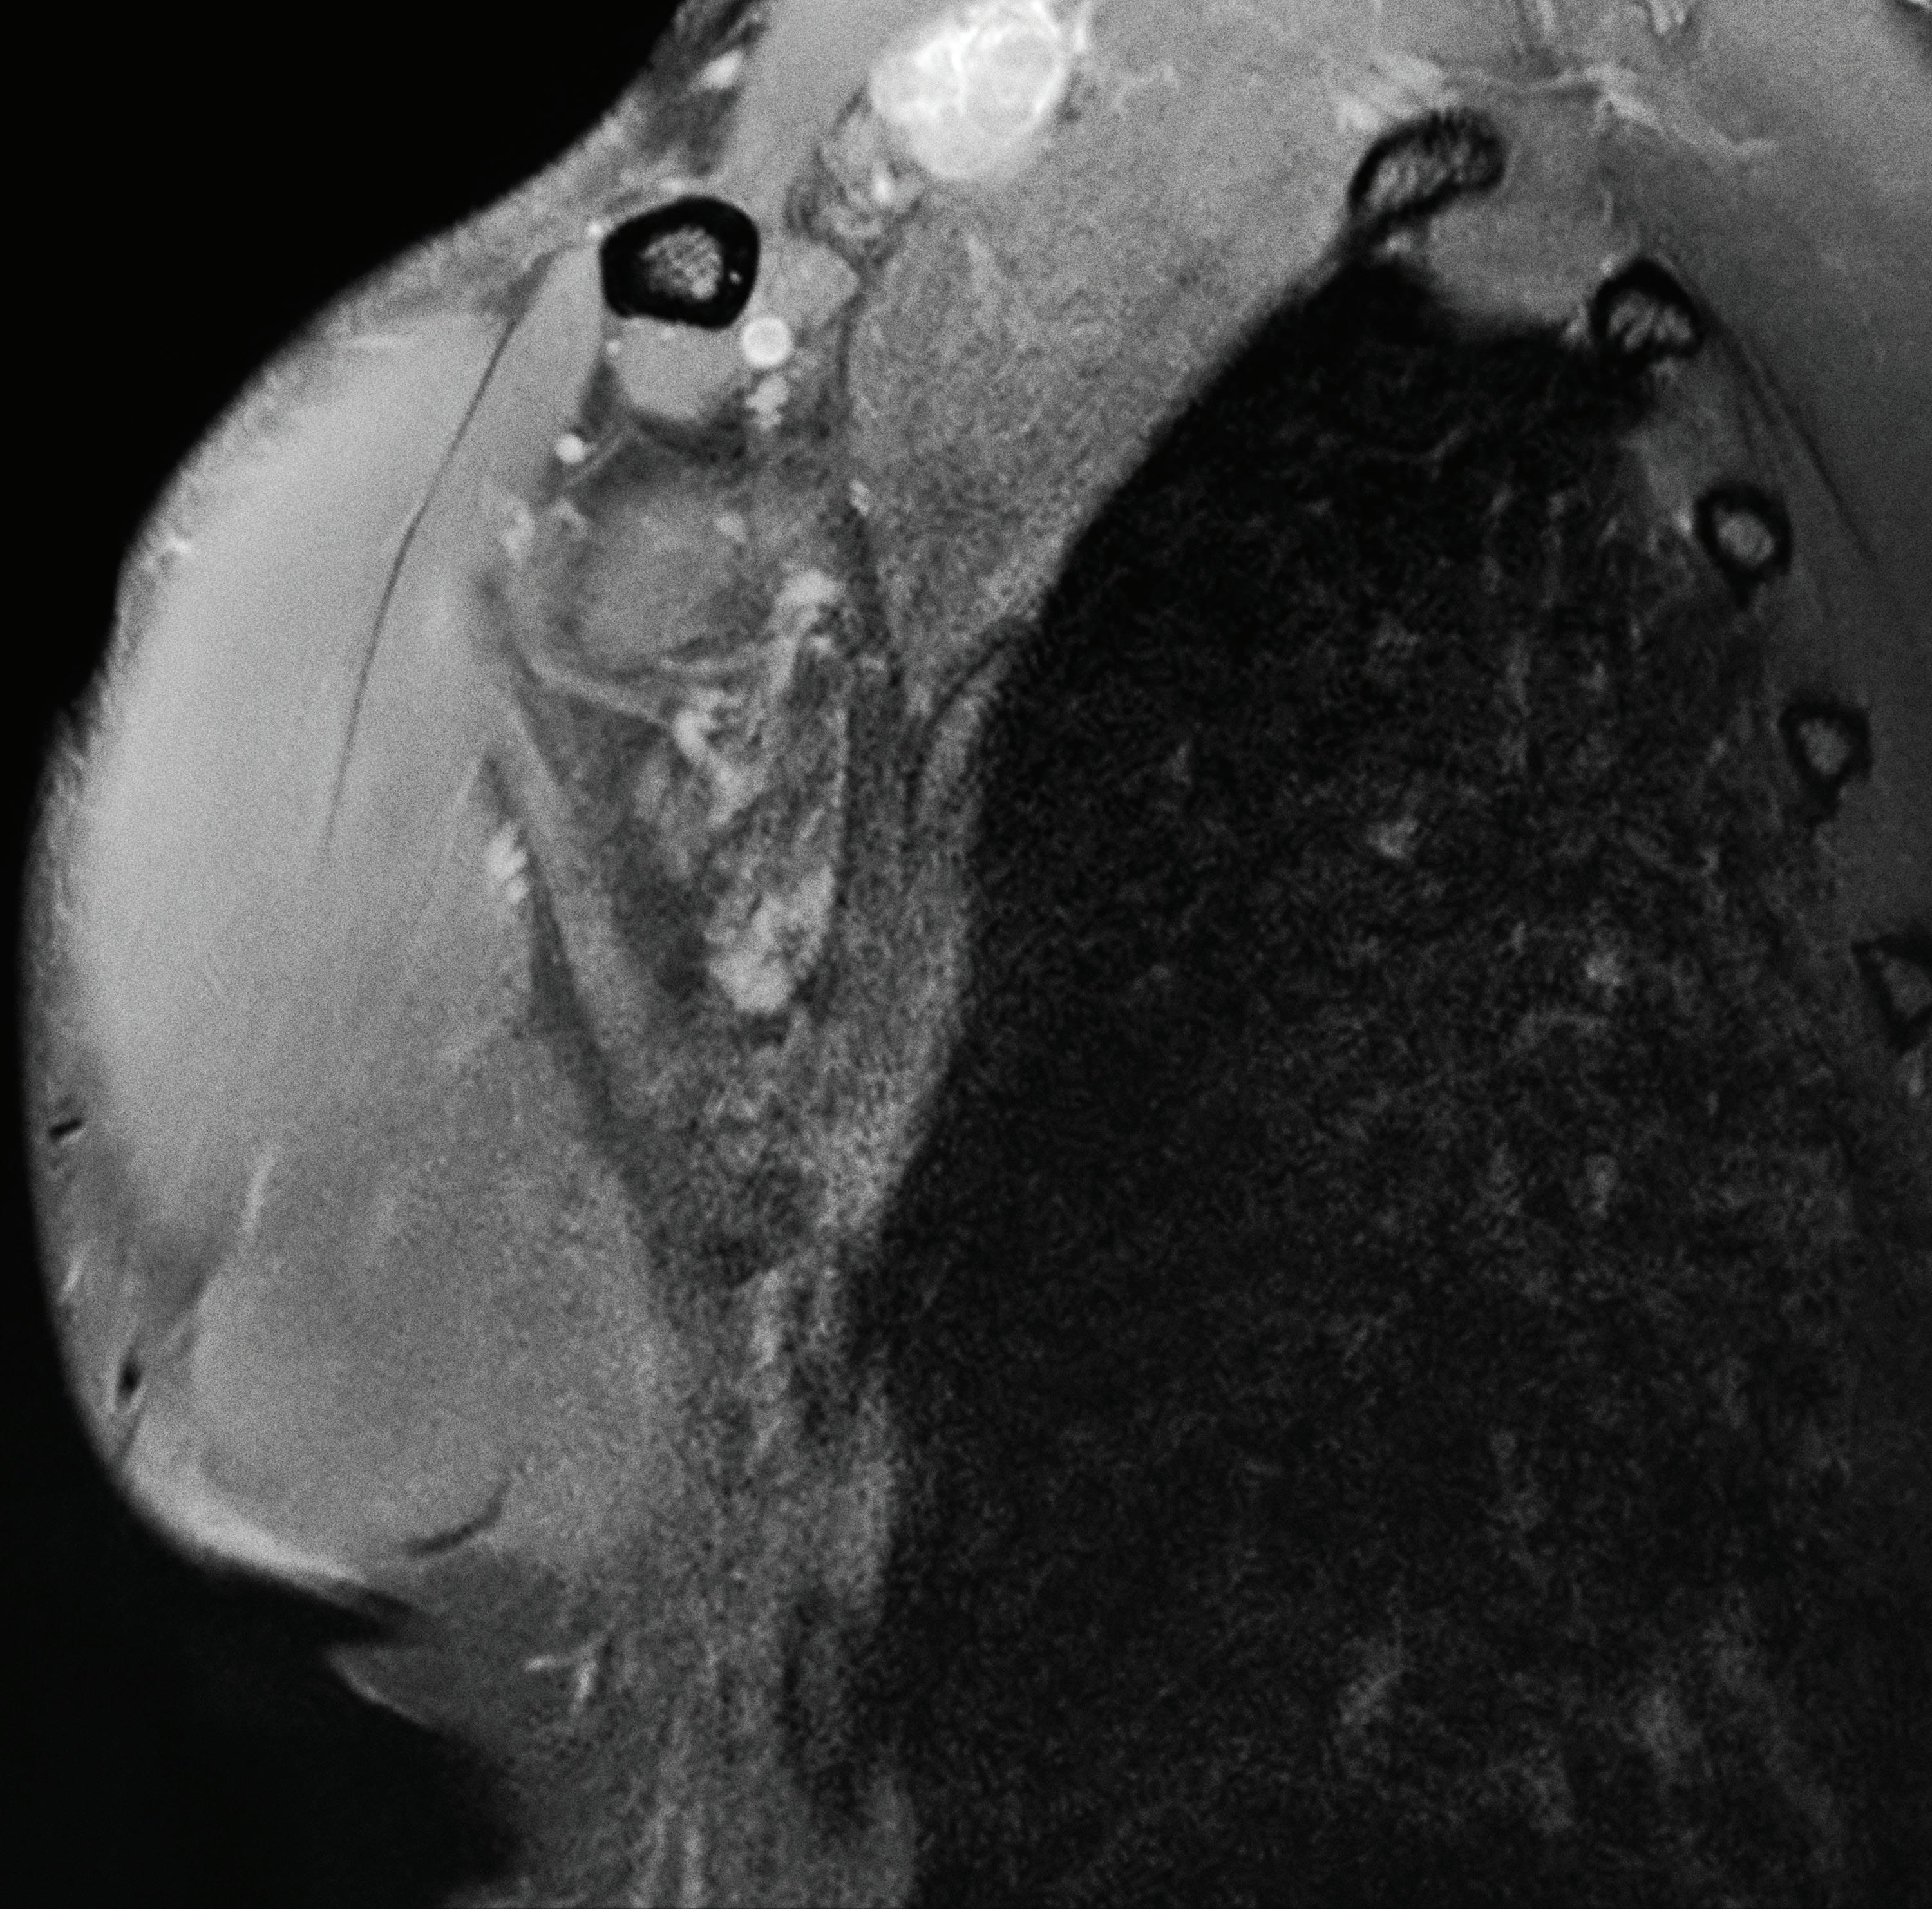

Primer MAMMOMAT Revelation en Argentina

Con tecnología de la más alta gama, nace “San Martín Mujer”

Diagnóstico Journal dialogó con el Dr. Alberto Grendene, especialista en diagnóstico por imágenes y coordinador del área de diagnóstico por imágenes del Sanatorio San Martín de Venado Tuerto, ubicado en el sur de la provincia de Santa Fe.

El especialista comentó que en lo que respecta al servicio de diagnóstico por imágenes, está distribuido en ambos edificios y cuenta con un equipamiento de vanguardia. Tienen con dos resonadores, dos tomógrafos multislice, radiología digital, siete ecógrafos, densitómetro, equipo de hemodinamia y con el mamógrafo MAMMOMAT Revelation de Siemens Healthineers lograron elevar la calidad de los diagnósticos mamarios.

“En relación a San Martín Mujer, hemos renovado nuestro densitómetro y adquirido un ecógrafo de última generación, especialmente orientado a la salud femenina. Además, hemos reemplazado nuestro mamógrafo por un equipo Mamomat Revelation (El primero en funcionar dentro de Argentina) de Siemens Healthineers.” Según el profesional, la actualización de los equipos representan una evolución en la calidad de imagen y la comodidad

para las pacientes que alli se atienden. “Al implementar este nuevo equipo desde Marzo, hemos tenido notables resultados. Nuestros técnicos se adaptaron rápidamente a la operación del mismo, lo que ha optimizado su desempeño. Nuestros médicos, tanto los que informan como los derivantes, han expresado su satisfacción con la calidad de imagen que ofrece el equipo, lo que ha influido en un incremento significativo en el número de estudios realizados. En cuanto al servicio posventa, tanto Farkim como Siemens han brindado un soporte eficiente y atento a nuestras necesidades.

Es relevante subrayar que el Sanatorio San Martín de Venado Tuerto es pionero en Argentina y a nivel global en la realización de tomosíntesis con un ángulo de 50 grados. Esta inversión representa un salto significativo en la detección y diagnóstico temprano del cáncer de mama. “Nuestro objetivo es equipararnos a los centros de salud más destacados del país, no en competencia, sino como una oferta de calidad para nuestra extensa región. Estamos comprometidos en brindar a nuestra población acceso a servicios de salud de primer nivel”.

Desde Siemens Healthineers, las especialistas Ana Paula Francisqueti, especialista clínica de Siemens Healthinners y Roxana Bucholz, Product Manager de Mamografía de Siemens Healthineers, manifiestan que a partir de la adquisición del mamógrafo MAMMOMAT Revelation, el Sanatorio San Martín ofrece a las pacientes con cáncer de mama acceso a una detección más precisa del cáncer.

La alta tecnología con equipo MAMMOMAT Revelation (con Tomosíntesis) termina siendo más efectiva para eliminar tejidos superpuestos; cuenta con herramienta para clasificación 100% objetiva y automatizada de la densidad mamaria directamente en la sala de examen, accesibilidad para biopsia guiada por un ángulo de 50° con radiografía de los fragmentos en 20s, sin mover al paciente. El mamógrafo ofrece a los pacientes compresores anatómicos para mayor comodidad y tecnología que puede reducir hasta un 30% de la dosis de radiación sin comprometer la calidad de imagen. El avance tecnológico con MAMMOMAT Revelation 3D hace que las anomalías se detecten de forma rápida y sencilla, proporcionando claridad para un diagnóstico seguro y una decisión terapéutica acertada. Precisión y confianza para detectar y diagnosticar con éxito el cáncer de mama, mejorar los resultados de los pacientes y las soluciones de imágenes con métodos innovadores.

El cual indica que la tecnología de 50°grados de angulación demuestra clínicamente que en un estudio de detección de 14.848 mujeres, donde el objetivo principal del ensayo de tomosíntesis mamaria de Malmö (MBTST) fue investigar la precisión de la tomosíntesis (3D) mamaria digital de una vista en comparación con la mamografía digital estándar (2D) de dos vistas.

Llegando a la conclusión que la evidencia clínica demuestra que:

34% mayor tasa de detección de cáncer en mamografía digital 3D

43% mayor tasa de detección de cáncer invasivo

15% menor dosis de radiación

Hasta 40% menor fuerza de compresión